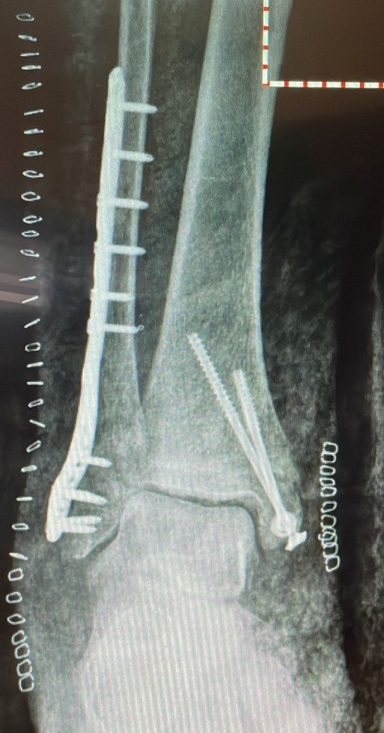

- Lateral Malleolus Fracture: Occurs when the distal portion of the fibula breaks, affecting the outer side of the ankle. This is the most common type of ankle fracture.

- Bimalleolar Fracture: This occurs when both the distal tibia and fibula are broken. It is the second most common type of ankle fracture.

- Post-surgery, a cast is worn for 30 days without weight-bearing.

- After 30 days, the cast is replaced, and partial weight-bearing of about 20 kg is allowed.

- After 60 days, the cast is removed, X-rays are performed, and a walker boot is provided. Rehabilitation begins, with gradual weight-bearing of about 50 kg for another 30 days.